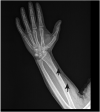

Case presentation: Here we report a case of benign subcutaneous emphysema after an insect bite on the hand of an 18-year-old Caucasian man. The puncture area in the first web space of his hand was erythematous and swollen. After 4 h, he began to hear crackling sounds in the hand. Although conservative management was provided, he experienced gradually increasing pain and rapid progression in swelling and crepitation. The symptoms regressed after fasciotomy.

Conclusion: This is the fourth reported case of benign subcutaneous emphysema after an insect bite in the literature. Although benign emphysema has a good prognosis after treatment, it is similar to necrotizing fasciitis. Proper diagnosis can only be established with histological and microbiological investigations, but in cases where early histological and microbiological investigations cannot be performed, biochemistry and radiological test should be used.